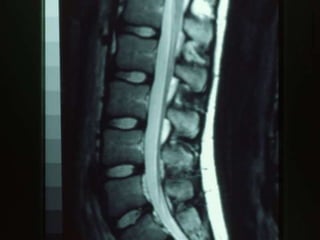

Age versus degenerative changes on MRI on

ASx patients